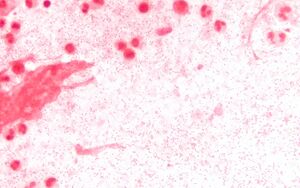

المستدميات النزلية عصورات Coccobacillus سلبية الغرام، وهي جراثیم هوائية عادة ولكن يمكن أن تكون لا هوائية مخيرة. ويحتاج نمو المستدميات النزلية في الزجاج إلى وجود عوامل نمو إضافية تشمل العامل Hemin) X) والعامل v (النيكوتيناميد أدنين دي نوكليوتيد (NAB)).

1. تلوين غرام: إن تلوين غرام لسوائل الجسم المخموجة قد يظهر وجود عصورات صغيرة سلبية الغرام مما يقترح وجود إصابة غازية بالمستدميات. ويجب زرع السائل الدماغي الشوكي والدم وسائل الجنب والسائل المفصلي والرشافة المأخوذة من الأذن الوسطى على أوساط زرع مناسبة. ويعتبر الزرع الإيجابي للمستدميات النزلية مؤكداً للتشخيص.